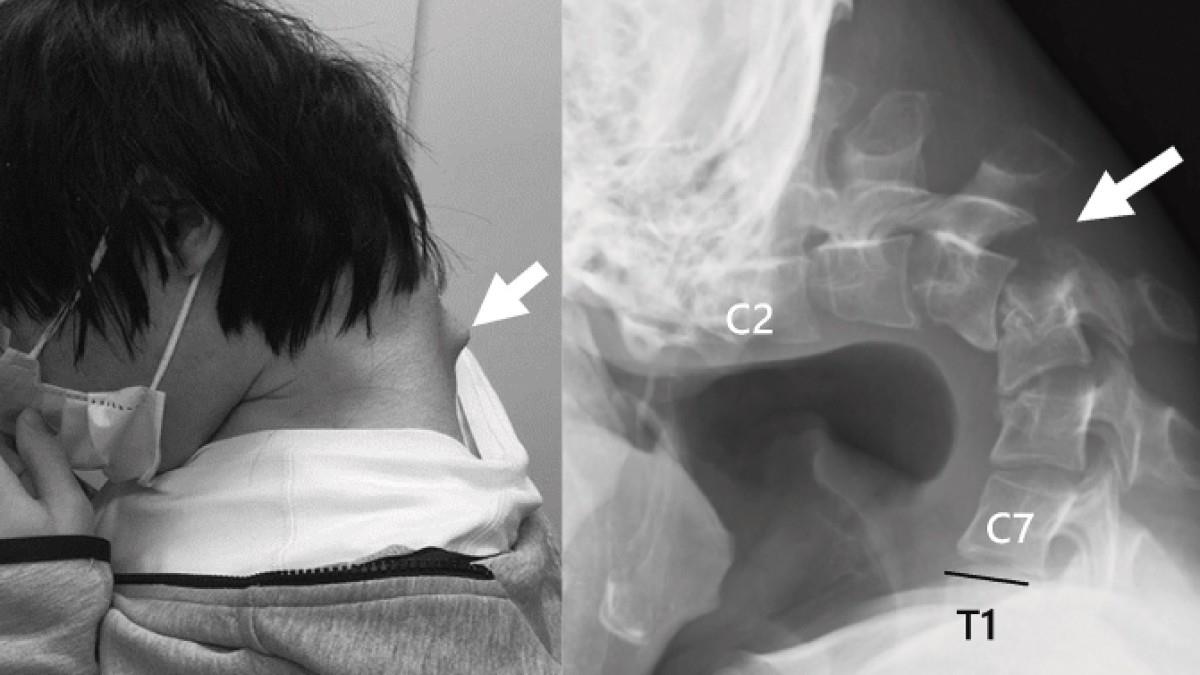

Αποτέλεσμα αυτής της στάσης ήταν να αναπτυχθεί ένα εξόγκωμα στον αυχένα, ενώ ο ίδιος έχασε πλήρως την ικανότητα να σηκώνει το κεφάλι του. Η κάμψη ήταν τόσο προχωρημένη, που το πηγούνι του ακουμπούσε μόνιμα στο στήθος.

Το 2023, ο νεαρός άρχισε να υποφέρει από αφόρητο πόνο στον αυχένα και δυσκολία στην κατάποση, η οποία προκάλεσε ταχεία απώλεια βάρους. Οι ιατρικές εξετάσεις αποκάλυψαν έντονη παραμόρφωση των αυχενικών σπονδύλων, καθώς και βλάβη στην ανώτερη σπονδυλική στήλη – συνέπειες της μακροχρόνιας καταπόνησης και υπερέκτασης των μυών του αυχένα.